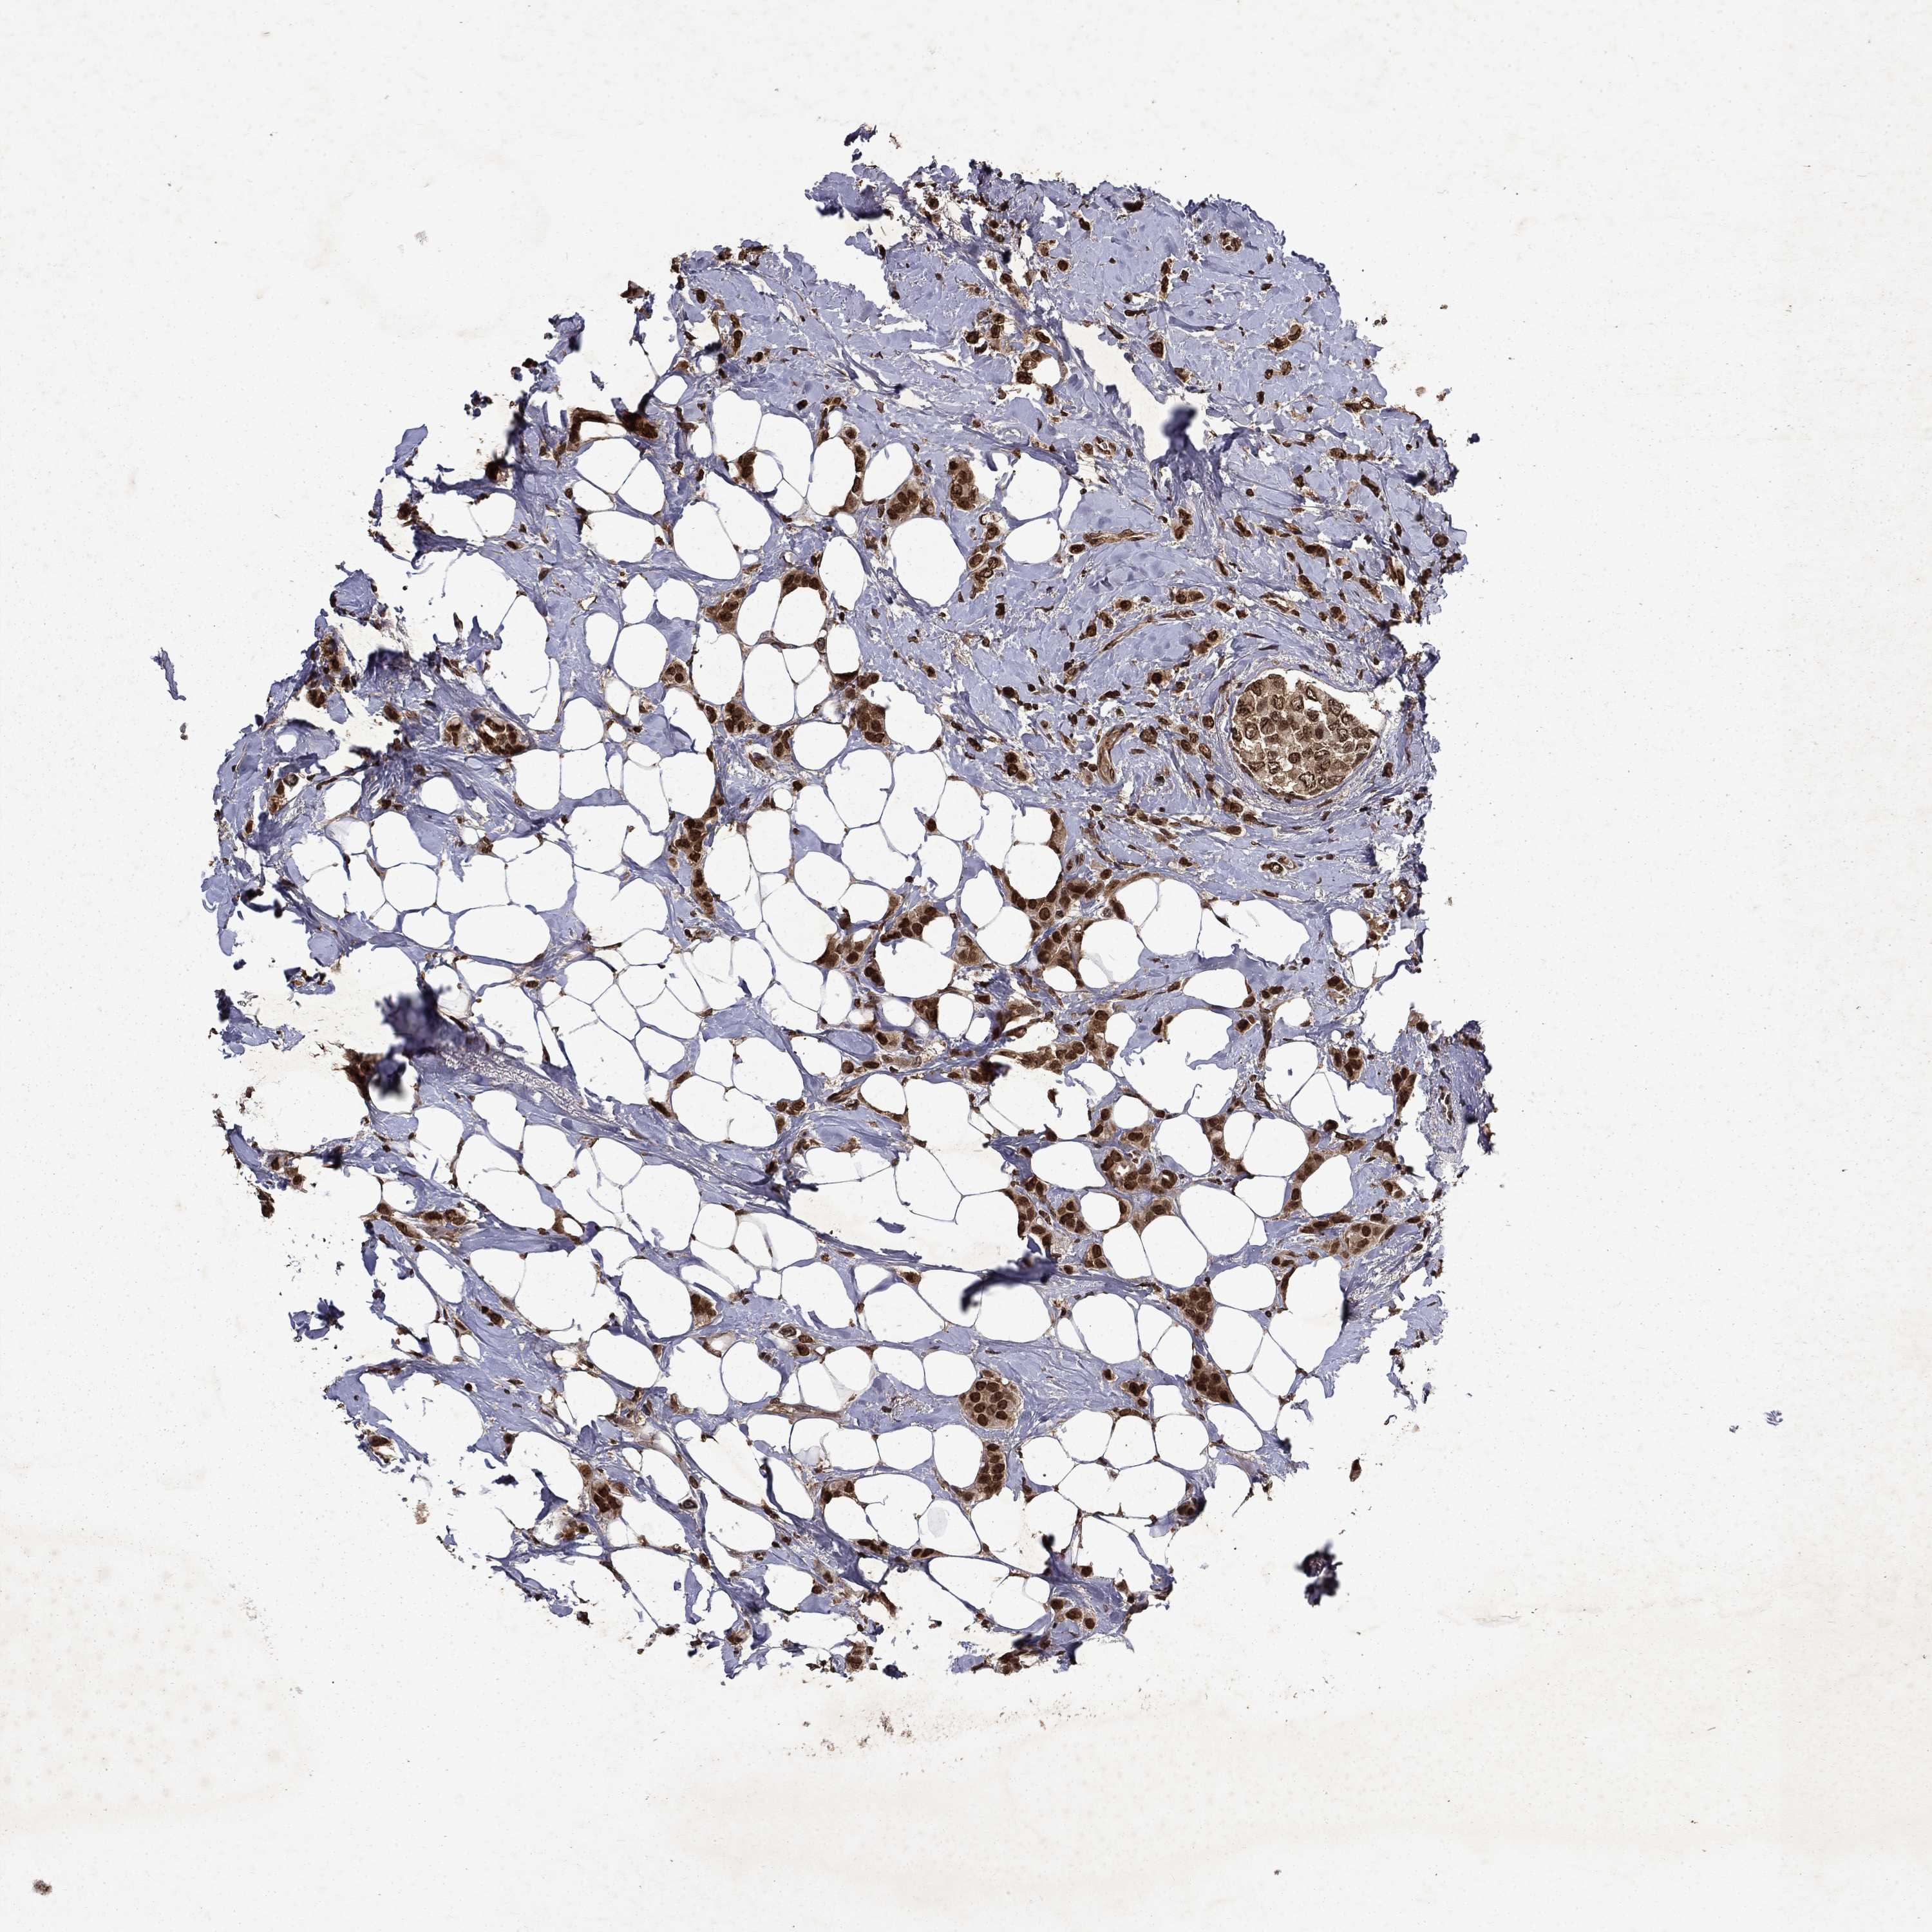

CANCER BREAST CANCER Show tissue menu

BRCA TCGA BRCA VALIDATION PROTEIN EXPRESSION

Breast cancer

Human cancer